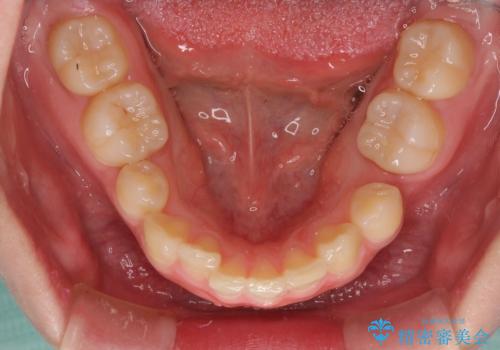

- 八重歯と下顎小臼歯の欠損を気にして来院された患者様です。

下顎小臼歯の欠損により過蓋咬合となっていたため、下顎は臼歯を起こすことで咬み合わせを改善し、八重歯は第一小臼歯2本を抜歯し、補助装置を使用して速やかに改善することとしました。

著しい過蓋咬合の改善が必要であった割には、治療期間は2年強と標準的でした。

八重歯は3,4か月で速やかに改善されました。